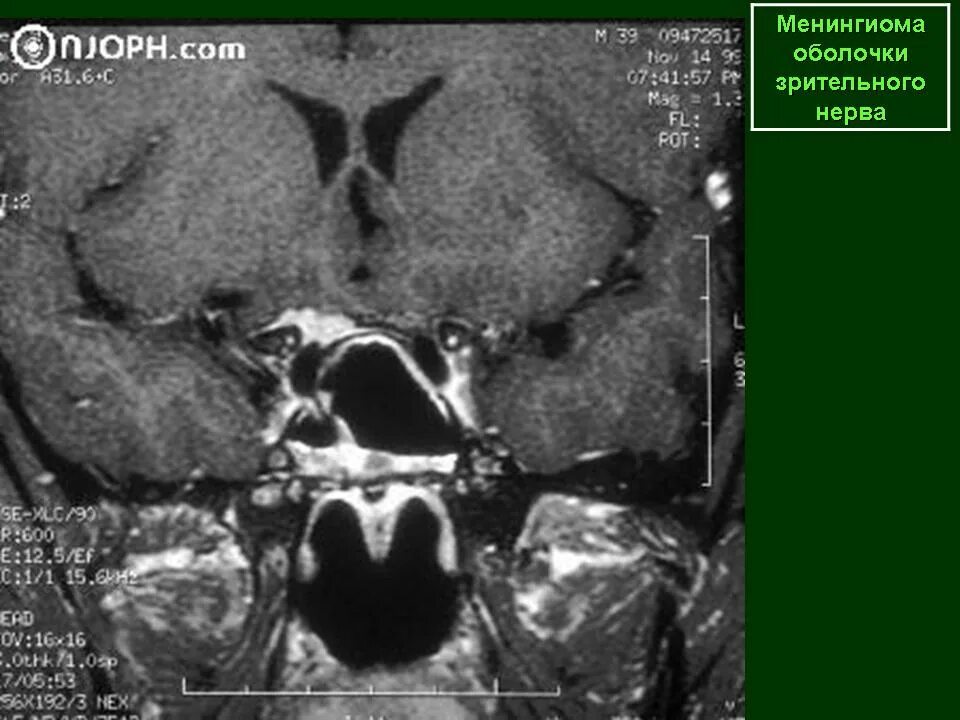

Менингиомы головного мозга мкб